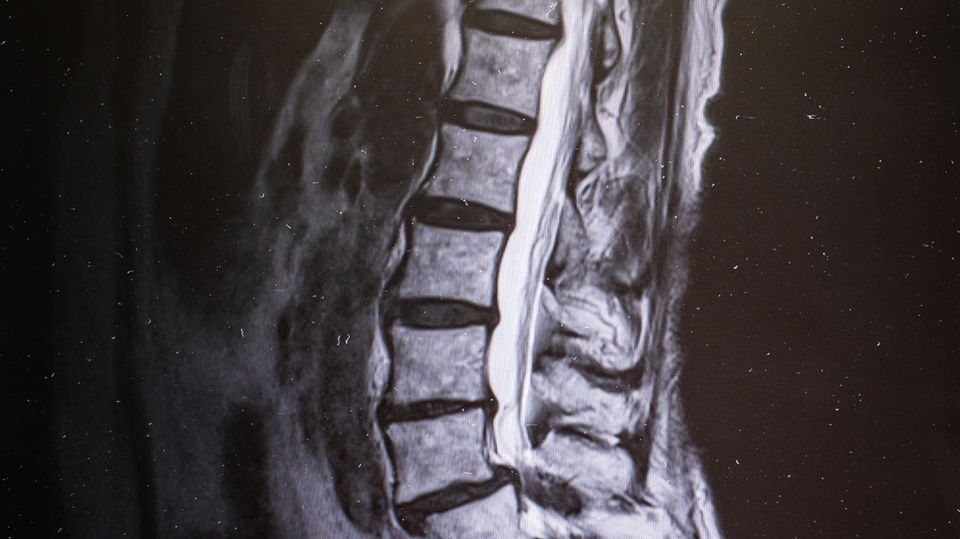

Er erklärte ihr das Leiden: Der Nervenkanal, der innerhalb der Wirbelsäule verläuft, war bei ihr im Bereich der Lendenwirbelsäule stark eingeengt. Teile der mit dem Alter porös gewordenen Bandscheiben drückten auf den Kanal sowie auf jene Bänder, die normalerweise die Wirbel stabil halten sollen. Auch sie hatten mit der Zeit ihre Elastizität verloren. Durch Verschleiß waren die kleinen Wirbelgelenke verdickt und knöcherne Höcker gewachsen, die ebenfalls auf die Nerven im Kanal drückten. Das verursachte die Schmerzen. Und: Wurden die Nerven besonders stark gequetscht, kam es zu blitzartigen Ausfällen der Nervenleitung, und die Muskeln in den Beinen erreichten für einen Moment keine Befehle. Geschah das beim Laufen, stolperte Weihe.

Zudem hatte sie eine in sich verdrehte Wirbelsäule und litt an einem Wirbelgleiten: Ein Wirbelkörper war verrutscht und bildete eine Stufe, die in den Nervenkanal hineinragte.